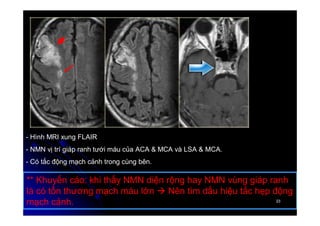

- Hình MRI xung FLAIR

- NMN vị trí giáp ranh tưới máu của ACA & MCA và LSA & MCA.

- Có tắc động mạch cảnh trong cùng bên.

** Khuyến cáo: khi thấy NMN diện rộng hay NMN vùng giáp ranh

là có tổn thương mạch máu lớn  Nên tìm dấu hiệu tắc hẹp động

mạch cảnh.